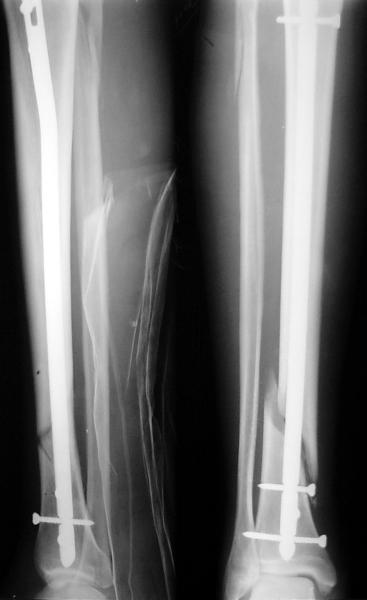

На мой взгляд, на снимках, приведённых Вами - неправильно сростающийся перелом дистальной трети большеберцовой кости, состояние после остеосинтеза интрамедуллярным гвоздём.

Как Вы пишите снимок под номером 1 - менсяц после операции, под номером 2- два месяца после операции.

Вы не послали послеоперационный снимок, поэтому трудно судить о состоянии редукции после операции.

Установка с медиальной стороны гвоздя в области дистального фрагмента дополнительного шурупа помогло бы Вам репонировать и удержать перелом в анатомическом положении, предотвратило варусную деформацию и смещение по ширине.

На мой взгляд внутрикостная фиксация переломов дистальной и проксимальной трети большеберцовой кости, за исключением поперечных, не очень хорошее решение вопроса, аппарат Илизарова или Тэйлора, позволяющие призвести закрытую анатомическую редукцию и отличное удержание отломков в период сращения.

I think that the X-Rays show S/P IMN of Spiral # of the Distal Tibia consoles in misalignment.

You wrote that a picture number 1 - f month after the surgery, and number 2-two months after the surgery.

You have not sent a postoperative X-Rays; so it's impossible to discuss about the condition of a reduction after operation.

Let to express concerning technique of operation my opinion... Insertion of a screw to medial side of a nail in distal fragment would help you to reduction and to keep this fracture in anatomic position has prevented varus deformity and displacement on width. By the way, if it is possible send a postoperative picture.

In my opinion IMN of fracture distal and proximal thirds of the tibia bones, except for transverse, not so good decision of treatment. Ilizarov or Taylor external fixators allow to the closed anatomic reduction and excellent fixation such fractures during the consolidation period.